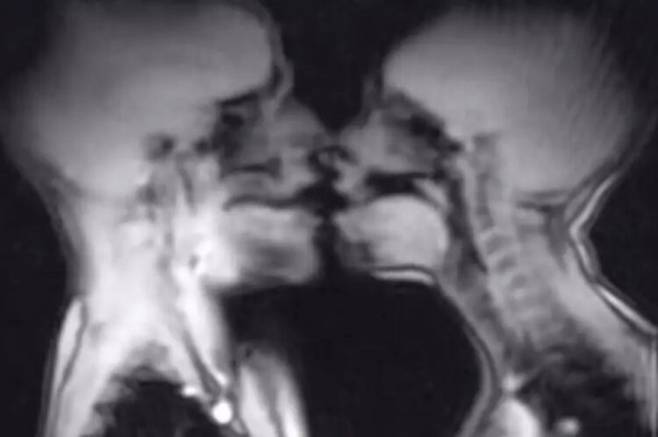

최근 영국 매체 미러가 보도한 이 실험은 1999년 ⟪영국의학저널(British Medical Journal)⟫에 발표돼 성관계 중 남녀 생식기의 실제 해부학적 변화를 영상으로 확인한 최초의 연구 중 하나로 평가된다. 연구진은 "성교 중 남성과 여성의 생식기를 MRI로 촬영하는 것은 가능하며, 인체 해부학에 대한 이해를 확장하는 데 기여한다"고 밝혔다.

MRI로 촬영한 영상 분석 결과, 발기한 음경은 부메랑 모양을 띠었고 전체 길이의 약 3분의 1이 골반 안쪽에 위치한 '음경 뿌리'로 구성돼 있다는 점이 확인됐다. 또한 여성의 성적 흥분 상태에서는 자궁이 위로 들어 올려지고 질 앞벽이 길어졌지만 자궁의 크기 자체는 커지지 않았다. 기존 해부학 교과서의 개념을 영상으로 입증한 결과였다.